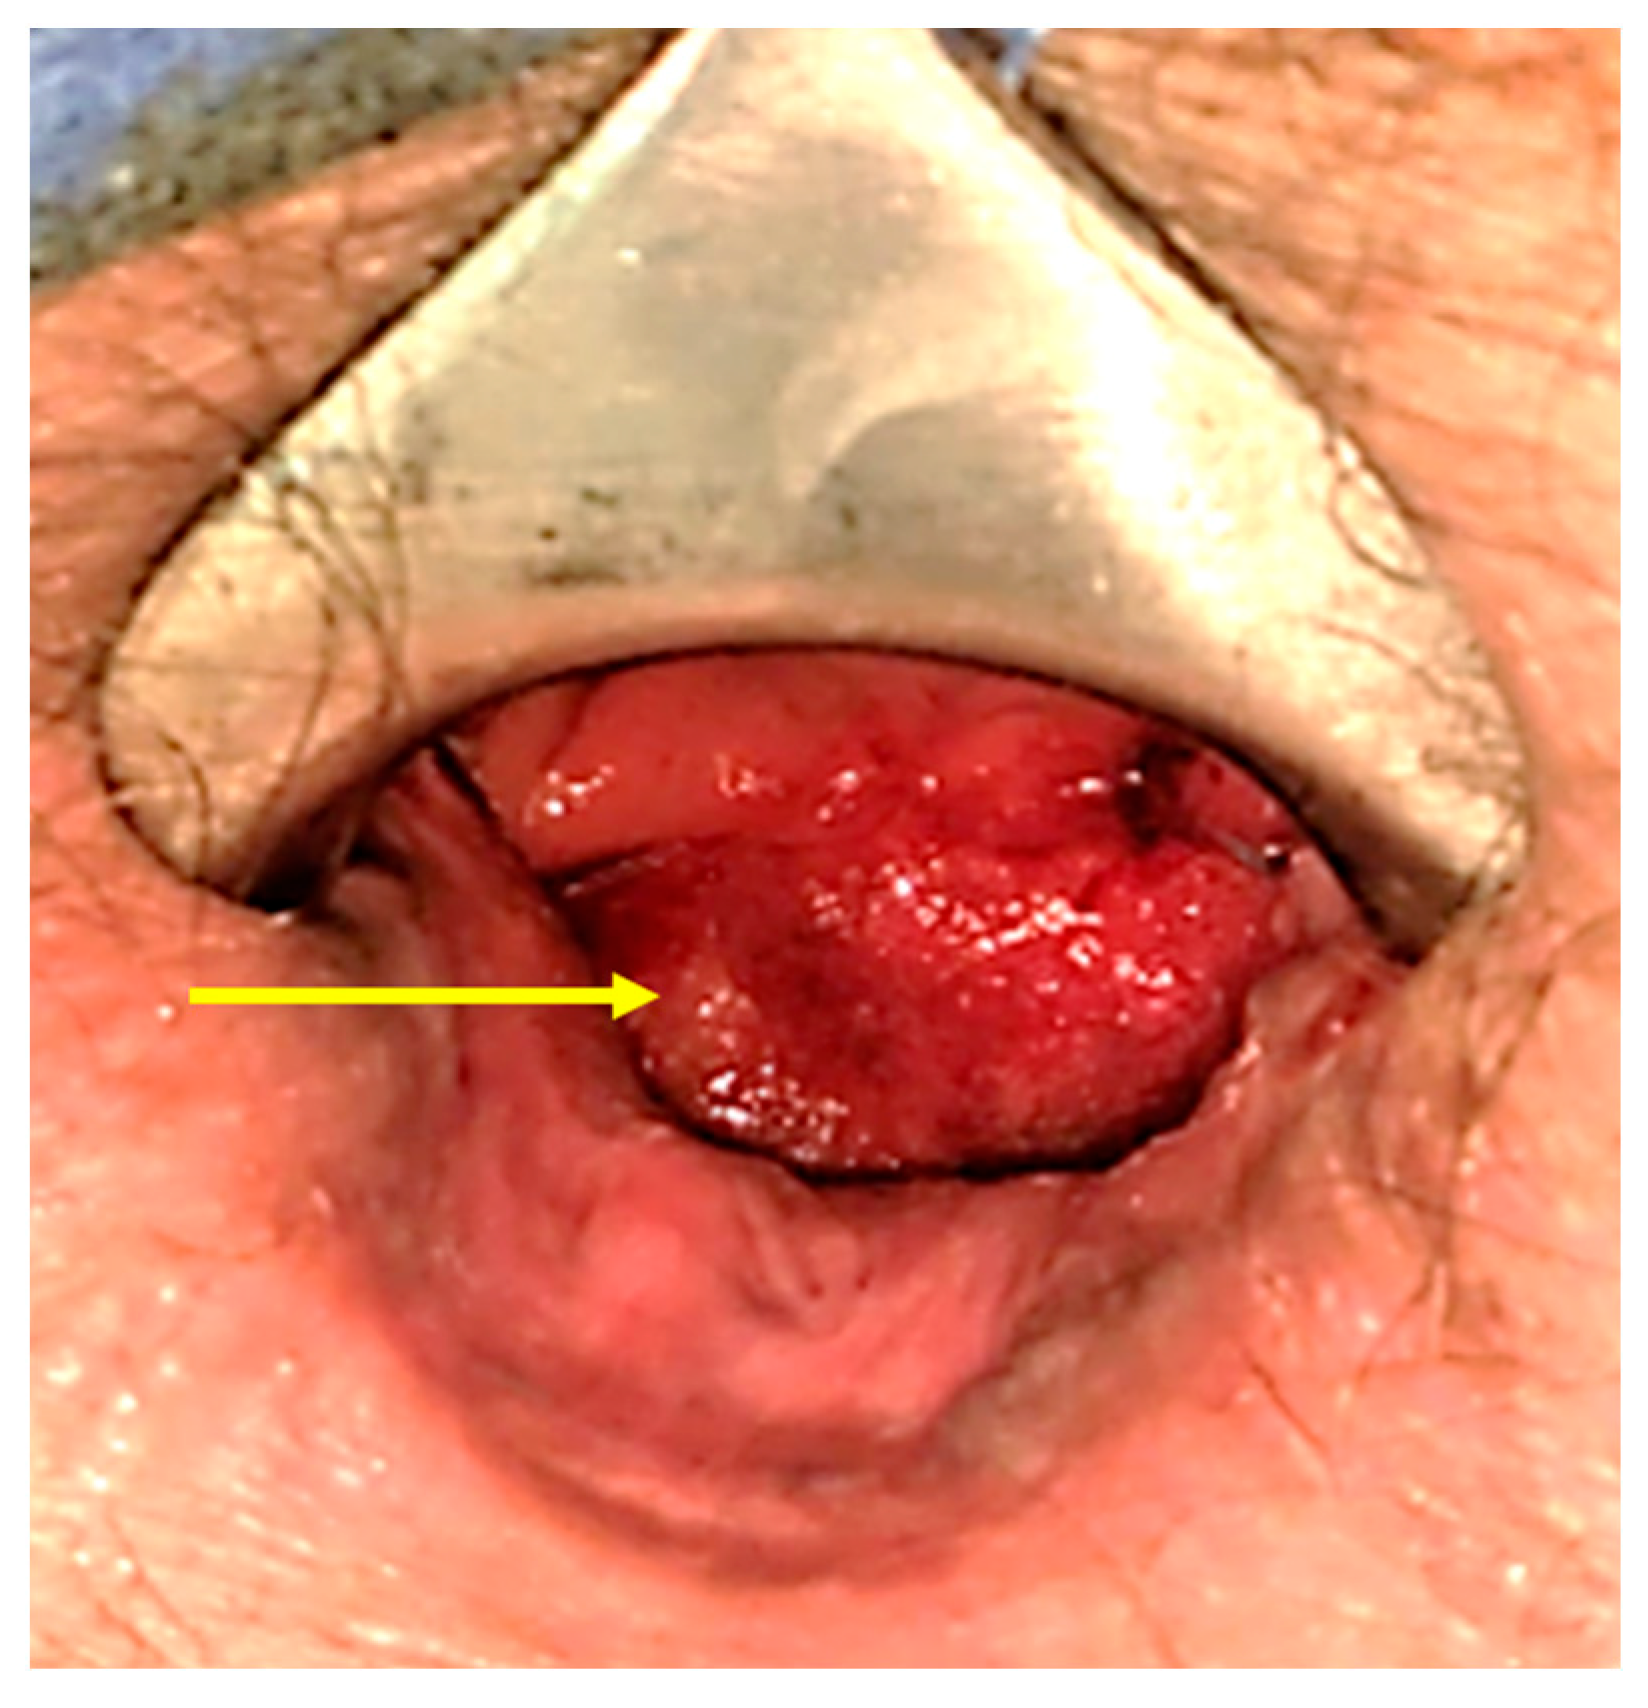

2. Detailed Case Description